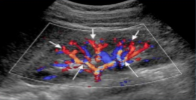

What vessels represented by the short white arrows?

What vessels are represented by the long white arrows?

Interlobar arteries

Segmental arteries